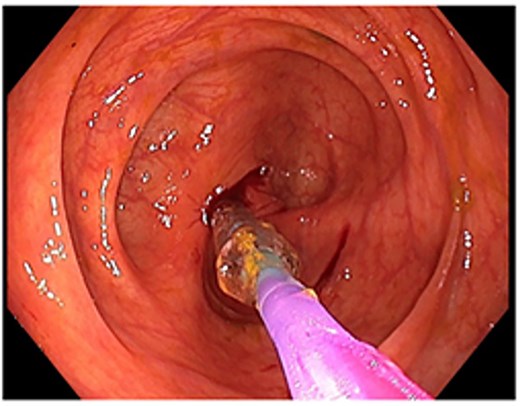

A 48-year-old lady with a background history of chronic migraines and family history of Crohn’s Disease presented to the emergency department with a three-day history of worsening abdominal pain and obstipation. She underwent a colonoscopy three days prior, which demonstrated shallow ulceration in the rectum and distal colon as well as a web-like stenosis in the ascending colon, 60 cm from the anal verge. The stenotic region was <5 mm in size and was unable to be traversed by the colonoscope, suspicious for a newly diagnosed stricturing Crohn’s disease (Fig. 1). She admitted to taking indomethacin suppositories 100 mg daily over the last two years for her migraines, as well as propranolol, triptan, ondansetron and sertraline. On examination her abdomen was soft, and tender in the right paraumbilical region without peritonism. Her haemoglobin was 94 g/L (115–165 g/L), C reactive protein (CRP) demonstrated a moderate inflammatory process at 40 mg/L (< 5 mg/L). Serum biochemistry and white cells were within normal limits. Computed tomography (CT) demonstrated a stricture in the ascending colon with an evolving proximal large bowel obstruction (Fig. 2). There was faecalisation in the terminal ileum suggestive of an acute on chronic obstruction. There was no suggestion of gastrointestinal perforation, or metastatic disease. The patient was made nil by mouth and prescribed intravenous hydrocortisone 100 milligrams four times a day by the gastroenterologist for suspected Crohn’s disease. However, the patient failed to progress after four days of hydrocortisone. A colonoscopic balloon dilatation was attempted with a 6 mm balloon, however the stricture appeared well-established, and the site began to bleed after the first attempt (Fig. 3). Subsequent attempts were abandoned due to the risk of bowel perforation. The distal end of the stricture was tattooed using spot ink. A colorectal surgeon became involved in her care who recommended a laparoscopic right hemicolectomy.

Colonoscopic picture of the diaphragm-like stricture in the ascending colon, 60 cm from the anal verge.